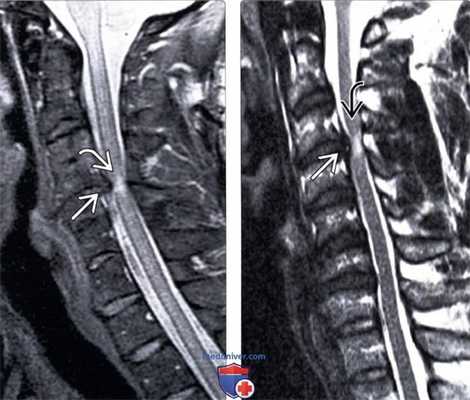

(Слева) На сагиттальном Т2-ВИ пациента с посттравматическим центральным спинномозговым синдром виден фокальный гиперинтенсивный сигнал спинного мозга на уровне С4-С5, свидетельствующий о контузии спинного мозга. Обратите внимание на признаки исходного стеноза спинномозгового канала за счет выраженных спондилофитов замы кательных пластинок позвонков на этом уровне.

(Справа) Т2-ВИ сагиттальная проекция: гиперинтенсивность сигнала спинного мозга на уровне С3-С4. В дополнение к врожденному стенозу спинномозгового канала у этого пациента имеет место протрузия диска СЗ-С4, ставшая причиной еще большего усугубления стеноза спинномозгового канала.